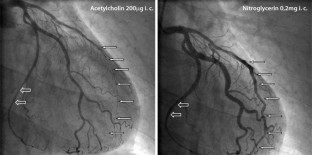

Abb. 1